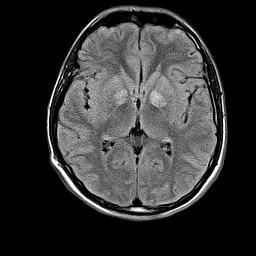

Eye of the Tiger Sign

• Symmetric low T2 signal of globus pallidus (due to accumulation of iron) with central area of high signal (due to gliosis)

• Associated with PKAN (pantothenate kinase associated neurodegeneration)

• Other associations

• Organophosphate poisoning

• Parkinsonism

• Wilson disease